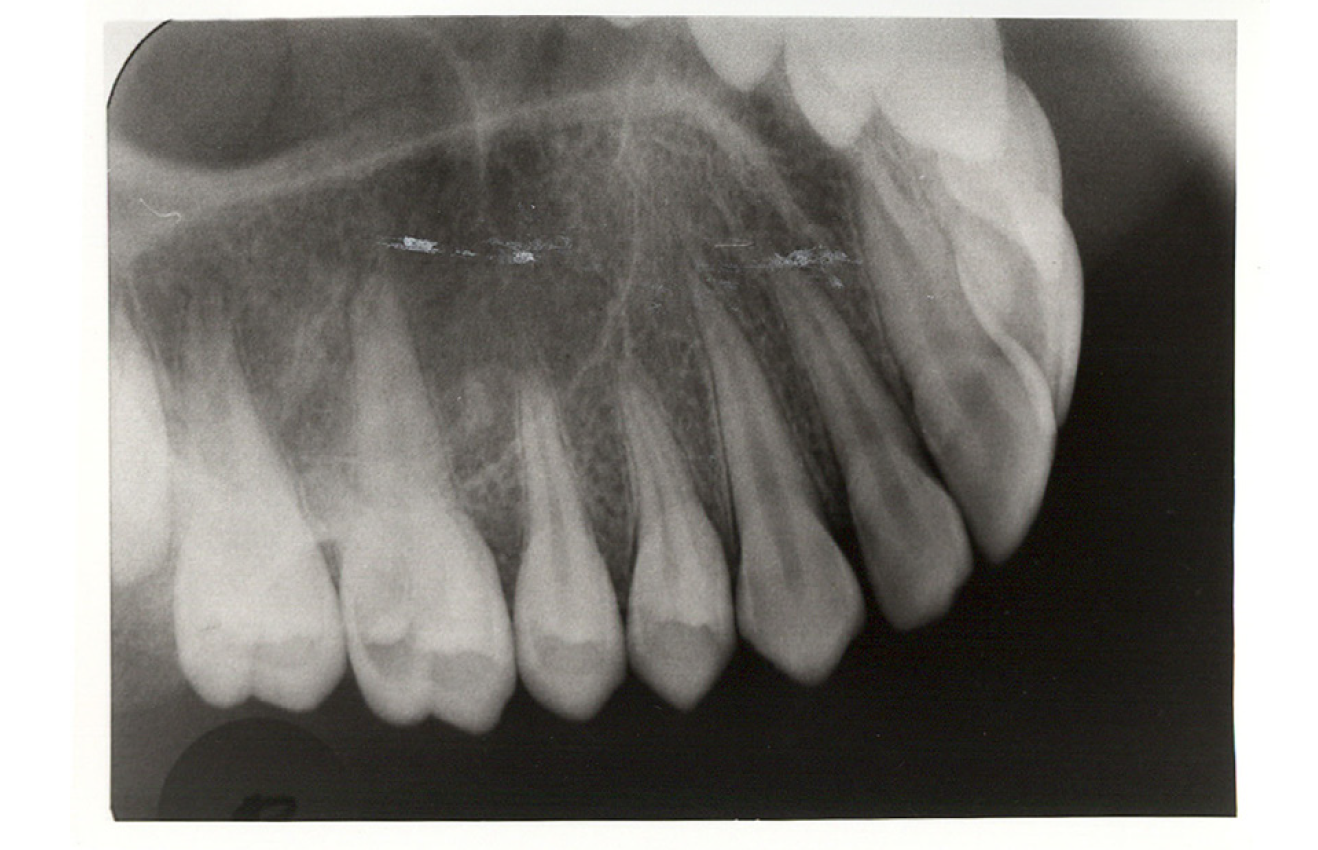

Bitewing examinations were introduced by Dr. Raper in 1925. Bitewing images focus on the clinical crowns of both the maxillary and mandibular teeth. Bitewings do not show the apices of the tooth and cannot be used to diagnose in this area. The greatest value of bitewing radio- graphic images is the detection of interproximal caries in the early stages of development, before it is clinically apparent. The arrows in Figure 2 indicate areas of interproximal caries. Bitewing images also reveal the size of the pulp chamber and the relative extent to which proximal caries have penetrated.

Figure 2 - Bitewing Images

Figure 2